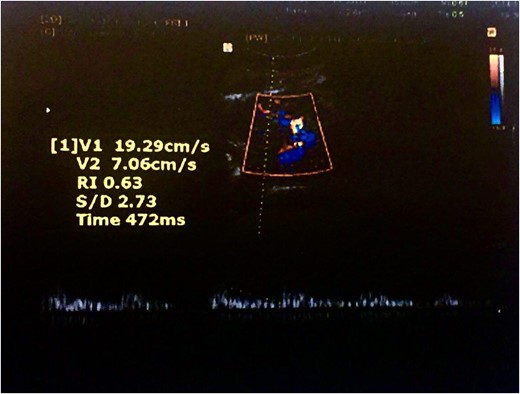

Color Doppler ultrasound of the transplanted kidney 2 months after surgery in the zoomed area of the image.